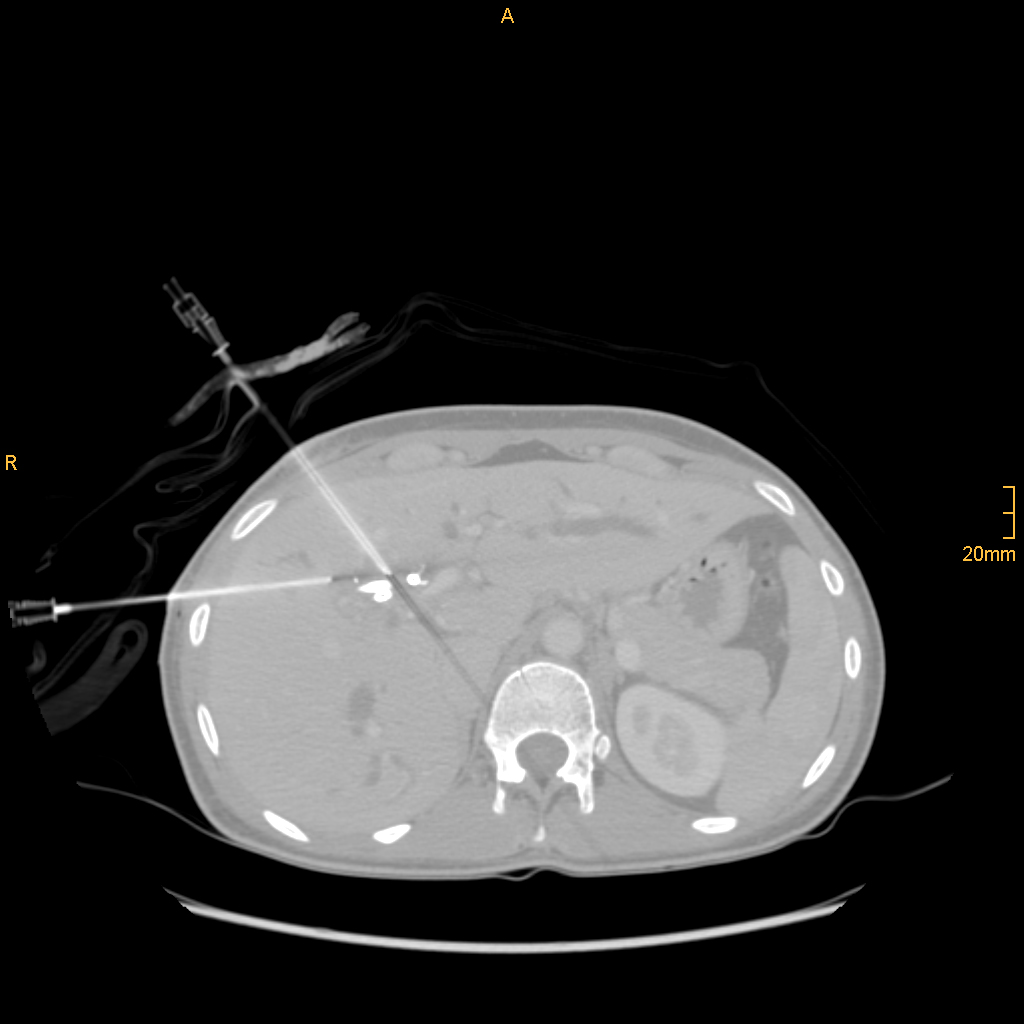

Nach Innsbruck kam Glodny aufgrund eines persönlichen Treffens mit o. Univ.-Prof. Dr. Werner Jaschke, dem Leiter der Innsbrucker Universitätsklinik für Radiologie. „Aus einem zunächst nur kurz angesetztem Termin bei ihm wurde ein mehrstündiges Gespräch, in dem ich erfahren habe, was hier in Innsbruck alles möglich ist und wie ich hier arbeiten kann“, erzählt Glodny rückblickend. Insbesondere die interventionelle Radiologie, durch die vielfältige therapeutische Eingriffe etwa in der Behandlung der arteriellen Verschlusskrankheit, oder von Blutungen oder Aneurysmen, von Tumoren- oder Metastasen möglich geworden sind, fasziniert den Radiologen und Forscher. „Mit durch Hochfrequenzstrom erzeugter Hitze, z. B. dem Verfahren der sogenannten Radiofrequenzablation, können Tumore oder Metastasen in Organen wie Leber, Niere oder Lunge behandelt werden. Die Vorteile dabei sind, dass ein oder mehrere Tumore extrem zielgenau und gründlich zerstört werden können, die ganze Prozedur aber für die PatientInnen sehr schonend ist. Die Absprache mit den behandelnden KollegInnen zur Erstellung eines individuellen interdisziplinären Behandlungskonzeptes für jede einzelne Patientin und jeden einzelnen Patienten garantiert die beste Versorgung.“ Am Standort Innsbruck schätzt Glodny vor allem das hohe fachliche Know How und gerät dabei nahezu ins Schwärmen: „Hier wird interventionelle Radiologie in absoluter Perfektion betrieben! Vor allem von Professor Reto Bale, der ein absoluter Experte auch in der Behandlung großer Tumore ist, kann ich sehr, sehr viel lernen. Darüber hinaus ist auch die Zusammenarbeit mit den KollegInnen aus der Universitätsklinik für Neuroradiologie unheimlich wertvoll und effektiv.“